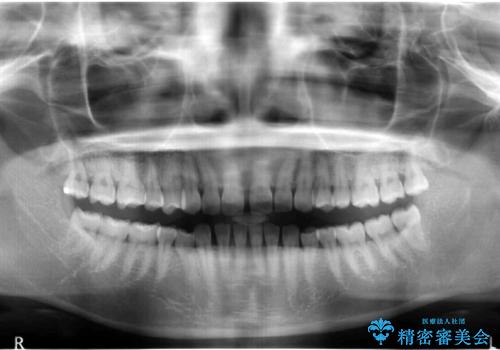

奥歯が1歯対1歯で、過蓋咬合を呈していました。

レントゲンで、右上4番の近心の垂直的骨欠損があり、抜歯を行うこととしました。

それがなければ上顎歯列の遠心移動をすることで、非抜歯でマウスピース矯正でも可能であったと思います。

short faceであり、結果上顎の臼歯を近心に大きくロスさせることになったたため、非常に長く治療期間はかかりました。